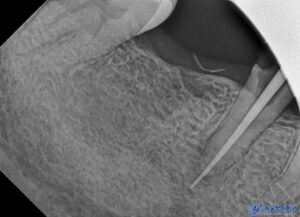

재신경치료의 경우,

이미 신경치료를 타 치과에서 진행했던 것을

다시 진행하는 것이기에

일반적인 신경치료보다 까다로워서

경험이 풍부한 의료진에게

받는 것이 중요합니다.

수정구치과 서울박사는

일반적으로 쓰이는 고무재료가 아닌,

고품질 MTA 재료를

신경치료에 사용하고 있습니다.

이렇게 기존의 재료들을 제거하고

재신경치료를 진행하였습니다.